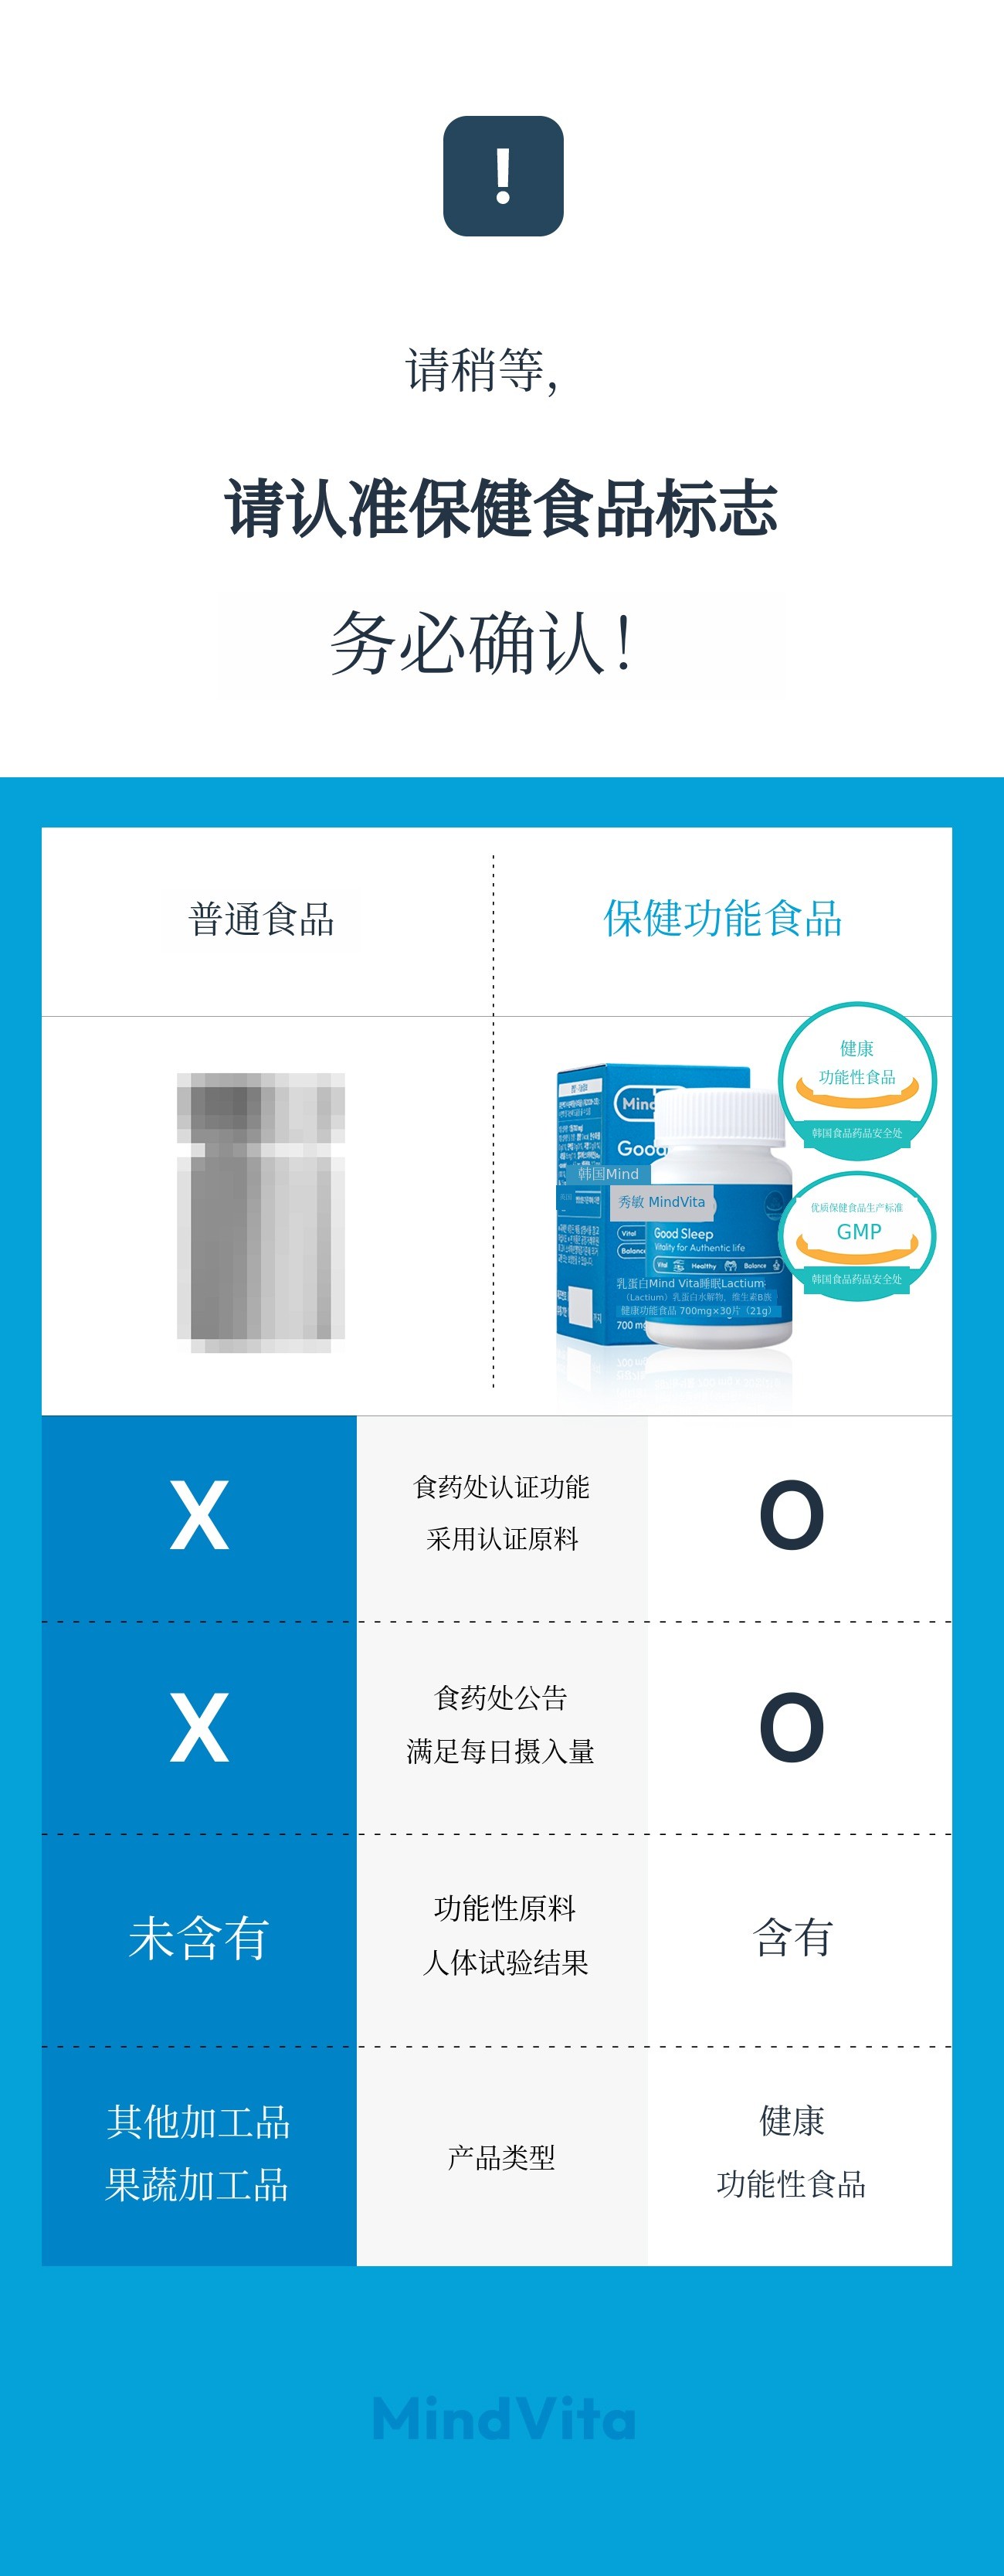

对药物副作用的担忧、咨询的时间和经济负担等,依然是想要开始管理心理健康的人们面前的巨大障碍。因此,我们思考要打造“人人都能无负担使用的睡眠护理解决方案”,答案就是专为心理健康设计的健康功能食品。 - 凝聚MindCafe专业性的‘MindVita’

‘MindVita’是以MindCafe积累的咨询数据和临床经验为基础,能够更简单安全地管理压力、情绪管理、睡眠等日常心理问题的健康功能食品品牌。本次通过Wadiz介绍的‘MindVita睡眠Lactium’是由守护数百万心理健康十年的心理健康平台MindCafe与精神健康医学科专家共同研究配比开发的心理护理睡眠营养补充剂。